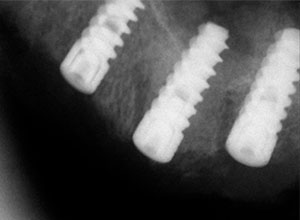

Radiografías periapicales donde se observa la posición de los implantes.